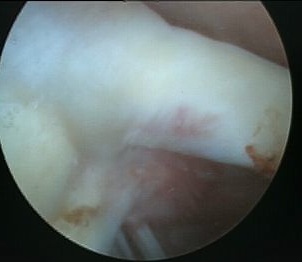

Sublabral foramen / recess

Normal variant

- recess under superior labrum

- this area of glenoid has no evidence of trauma with normal cartilage

- superior labrum and biceps anchor intact and stable

Sublabral foramen with stable biceps anchor